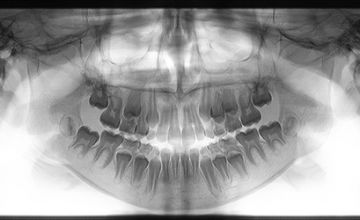

Ortopantomografia

Uma Ortopantomografia, também conhecida como radiografia panorâmica ou radiografia panorâmica da mandíbula, é um exame de imagem que fornece uma visão panorâmica dos dentes, mandíbula e estruturas adjacentes. É frequentemente usado na medicina dentária para avaliar a saúde oral e identificar possíveis problemas dentários.